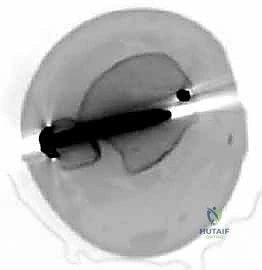

In clinical scenarios where the displacement is borderline (exactly 2 mm) or the integrity of the articular hinge remains questionable, intraoperative arthrography is a powerful adjunct. Arthrography allows dynamic, real-time visualization of the cartilaginous surfaces. If radiopaque dye does not leak into the joint space across the fracture line, the cartilaginous hinge is intact, and closed reduction with percutaneous pinning (CRPP) may be safely attempted. Advanced imaging, such as MRI, is rarely indicated in the acute setting but can be utilized in delayed presentations to assess physeal anatomy and vascularity.

The reduction must be assessed visually at the articular surface. Anatomic restoration of the radiocapitellar and ulnohumeral joint line is the primary, non-negotiable goal. Once the articular surface is perfectly congruent, the metaphyseal fracture line should also interdigitate anatomically. Fluoroscopy is then used to confirm the reduction on both true AP and lateral views prior to final fixation.